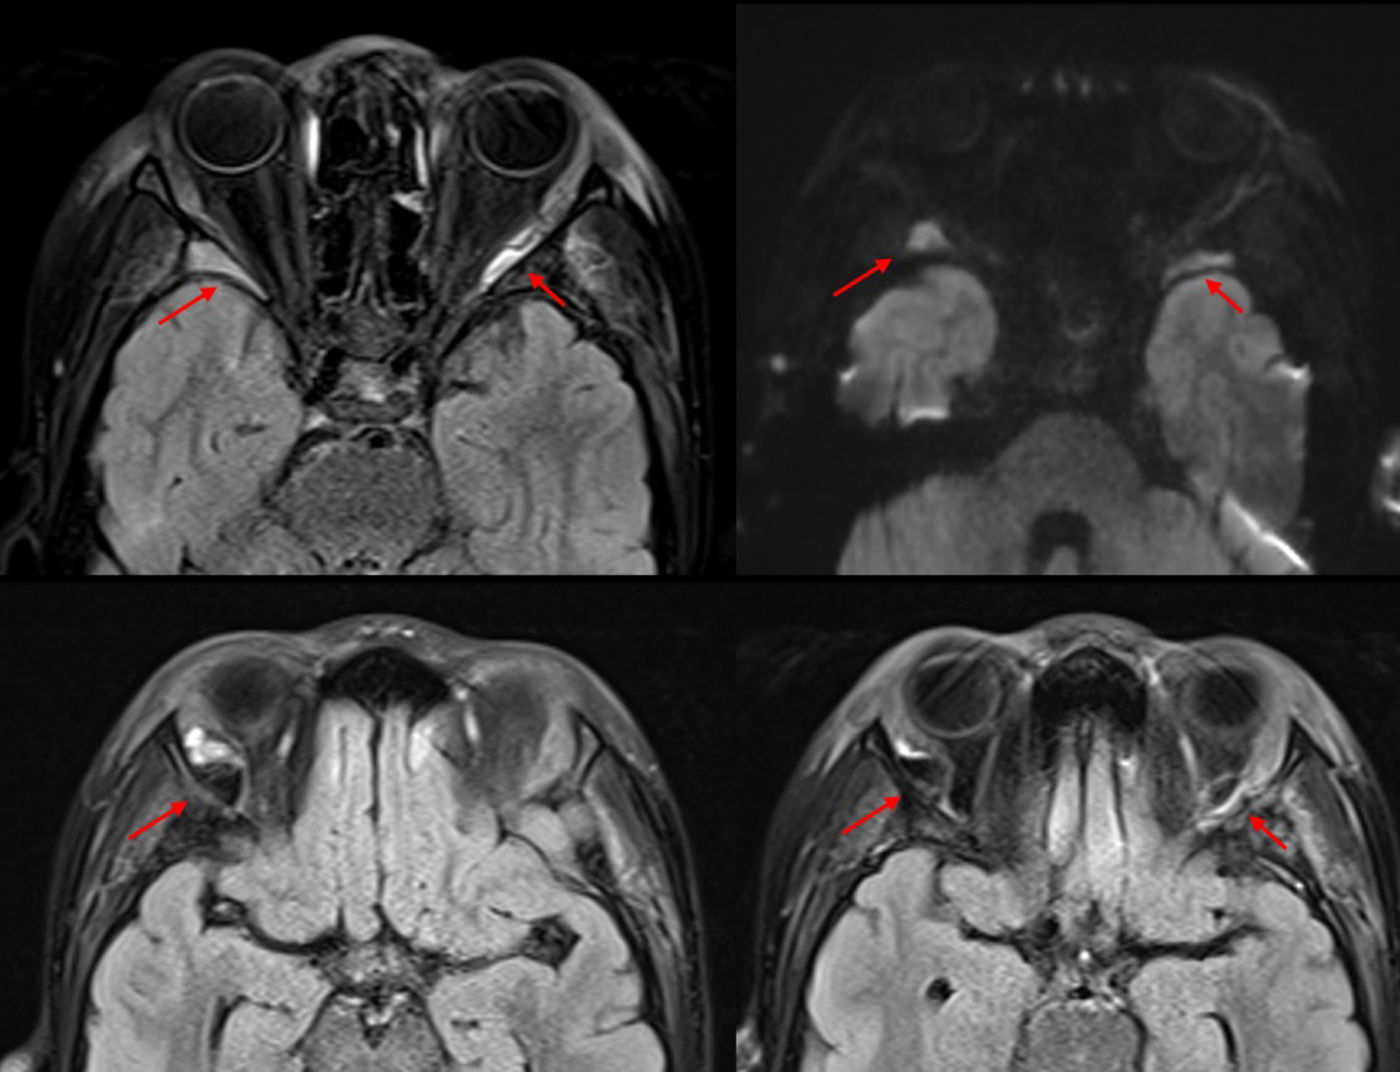

Paciente de 8 años con enfermedad de células falciformes homocigota (sin antecedentes familiares), tratada con amoxicilina profiláctica, hidroxiurea y ácido fólico, en seguimiento anual y con un ingreso previo por crisis vasooclusiva en pierna, sin otros antecedentes. Ingresa con sospecha de crisis vasooclusiva en extremidades y abdominalgia en hospital de origen, y se deriva a nuestro centro por deterioro progresivo, con fiebre, hepatomegalia y esplenomegalia hasta cresta ilíaca, así como tumefacción dolorosa periocular bilateral, sin flogosis ni alteración visual (fig. 1). Analítica con descenso de hemoglobina y plaquetas, elevación de parámetros de hemólisis, HbS 44,3% y PCR de 17,7mg/dL. Sospecha de secuestro esplénico y celulitis orbitaria1,2, se administran oxigenoterapia, analgesia en perfusión contínua de morfina, dos transfusiones de hematíes y antibioterapia endovenosa. TAC de órbita (fig. 2) con componente de partes blandas en región periorbitaria externa bilateral, siguiendo el margen óseo y con extensión posterior, compatible con posible hematopoyesis extramedular o proceso linfoproliferativo. RMN craneal (fig. 3) descarta afectación nerviosa mostrando áreas sugestivas de infarto en alas mayores esfenoidales y efusiones hemorrágicas secundarias3. Hemocultivo y serología a VEB negativos. Se orienta como infarto óseo y se suspende antibioterapia, con mejoría clínica completa a los siete días.